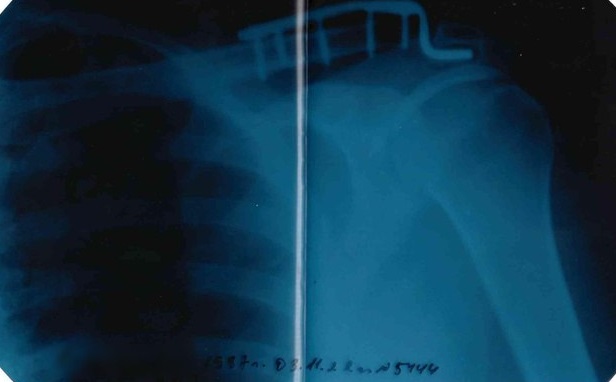

35-летнего жителя Красноярска Якова в сентябре мобилизовали, несмотря на металлическую пластину на месте травмированного сочленения лопатки и ключицы. В учебной части из-за усиленной нагрузки у него отнялась рука. Возвращать его домой командование отказывается – вместо необходимой операции его угрожают "отправить на спецоперацию".

– В 2013 году Яков попал в ДТП, разорвалось сочленение ключицы и лопатки, ему поставили на этом месте металлическую пластину с винтами. Почти 10 лет он жил с этой пластиной вполне нормально, так как плечо берег, не перегружал, – говорит мать мобилизованного Татьяна Николаевна (имя изменено по просьбе героини). – В конце сентября сыну пришла повестка, но никакой медкомиссии не было. Яков сказал в военкоматах (он в двух был – в Октябрьском и Железнодорожном районах) о пластине в плече, но его даже слушать не стали! Напротив, стали нагружать, как всех здоровых. Плечо стало болеть, а к началу ноября правая рука просто отнялась.

В начале ноября Якова направили в гражданский травмпункт в Херсонской области, где врач подтвердил, что требуется операция, и выдал справку о необходимости удалить металлоконструкцию.

Металлическая пластина в плече, рентген

– Вместо операции его перебросили в другой госпиталь, потом – в следующий. Наконец он оказался в Пскове, по месту прикрепления к воинской части. Там ему сказали, что можно "встать в очередь на плановую операцию". По сути это значит – нескорую операцию – не раньше мая 2023 года. И бог бы с этим, но ждать операции в госпитале или дома ему не разрешили. Приказали возвращаться на фронт! – возмущается мать Якова. – Сын подал рапорт командиру части, что не может нести службу – рука-то не работает. Просил отпустить на лечение по месту жительства. Ему отказали.